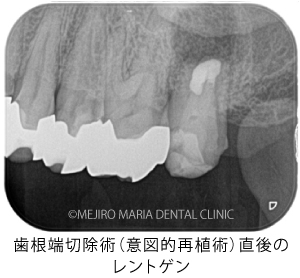

目白マリア歯科|【症例】歯根端切除術(意図的再植術)により、病変の大きい根尖性歯周炎の抜歯を回避|治療詳細_歯根端切除術(意図的再移植術)直後のレントゲン画像

当院で精密根管治療を施しましたが、瘻孔(フィステル・サイナストラクト)を消失させることが難しく、追加処置として歯根端切除術(今回は意図的再植術)を行いました。また、術前に撮影したCT画像より、根尖性歯周炎が原因と考えられる上顎洞炎(蓄膿症/ちくのうしょう)の併発も確認できました。

歯根端切除術(意図的再植術)から3週間後の経過観察で、瘻孔の消失が確認できました。また、術後3ヶ月経つと、根尖部付近に確認できていた根尖性歯周炎も小さくなりました。患者様も「噛んだときにも、違和感や痛みなどはない」ということで、予後は良好だと判断しました。今後は最終補綴処置を行う予定です。